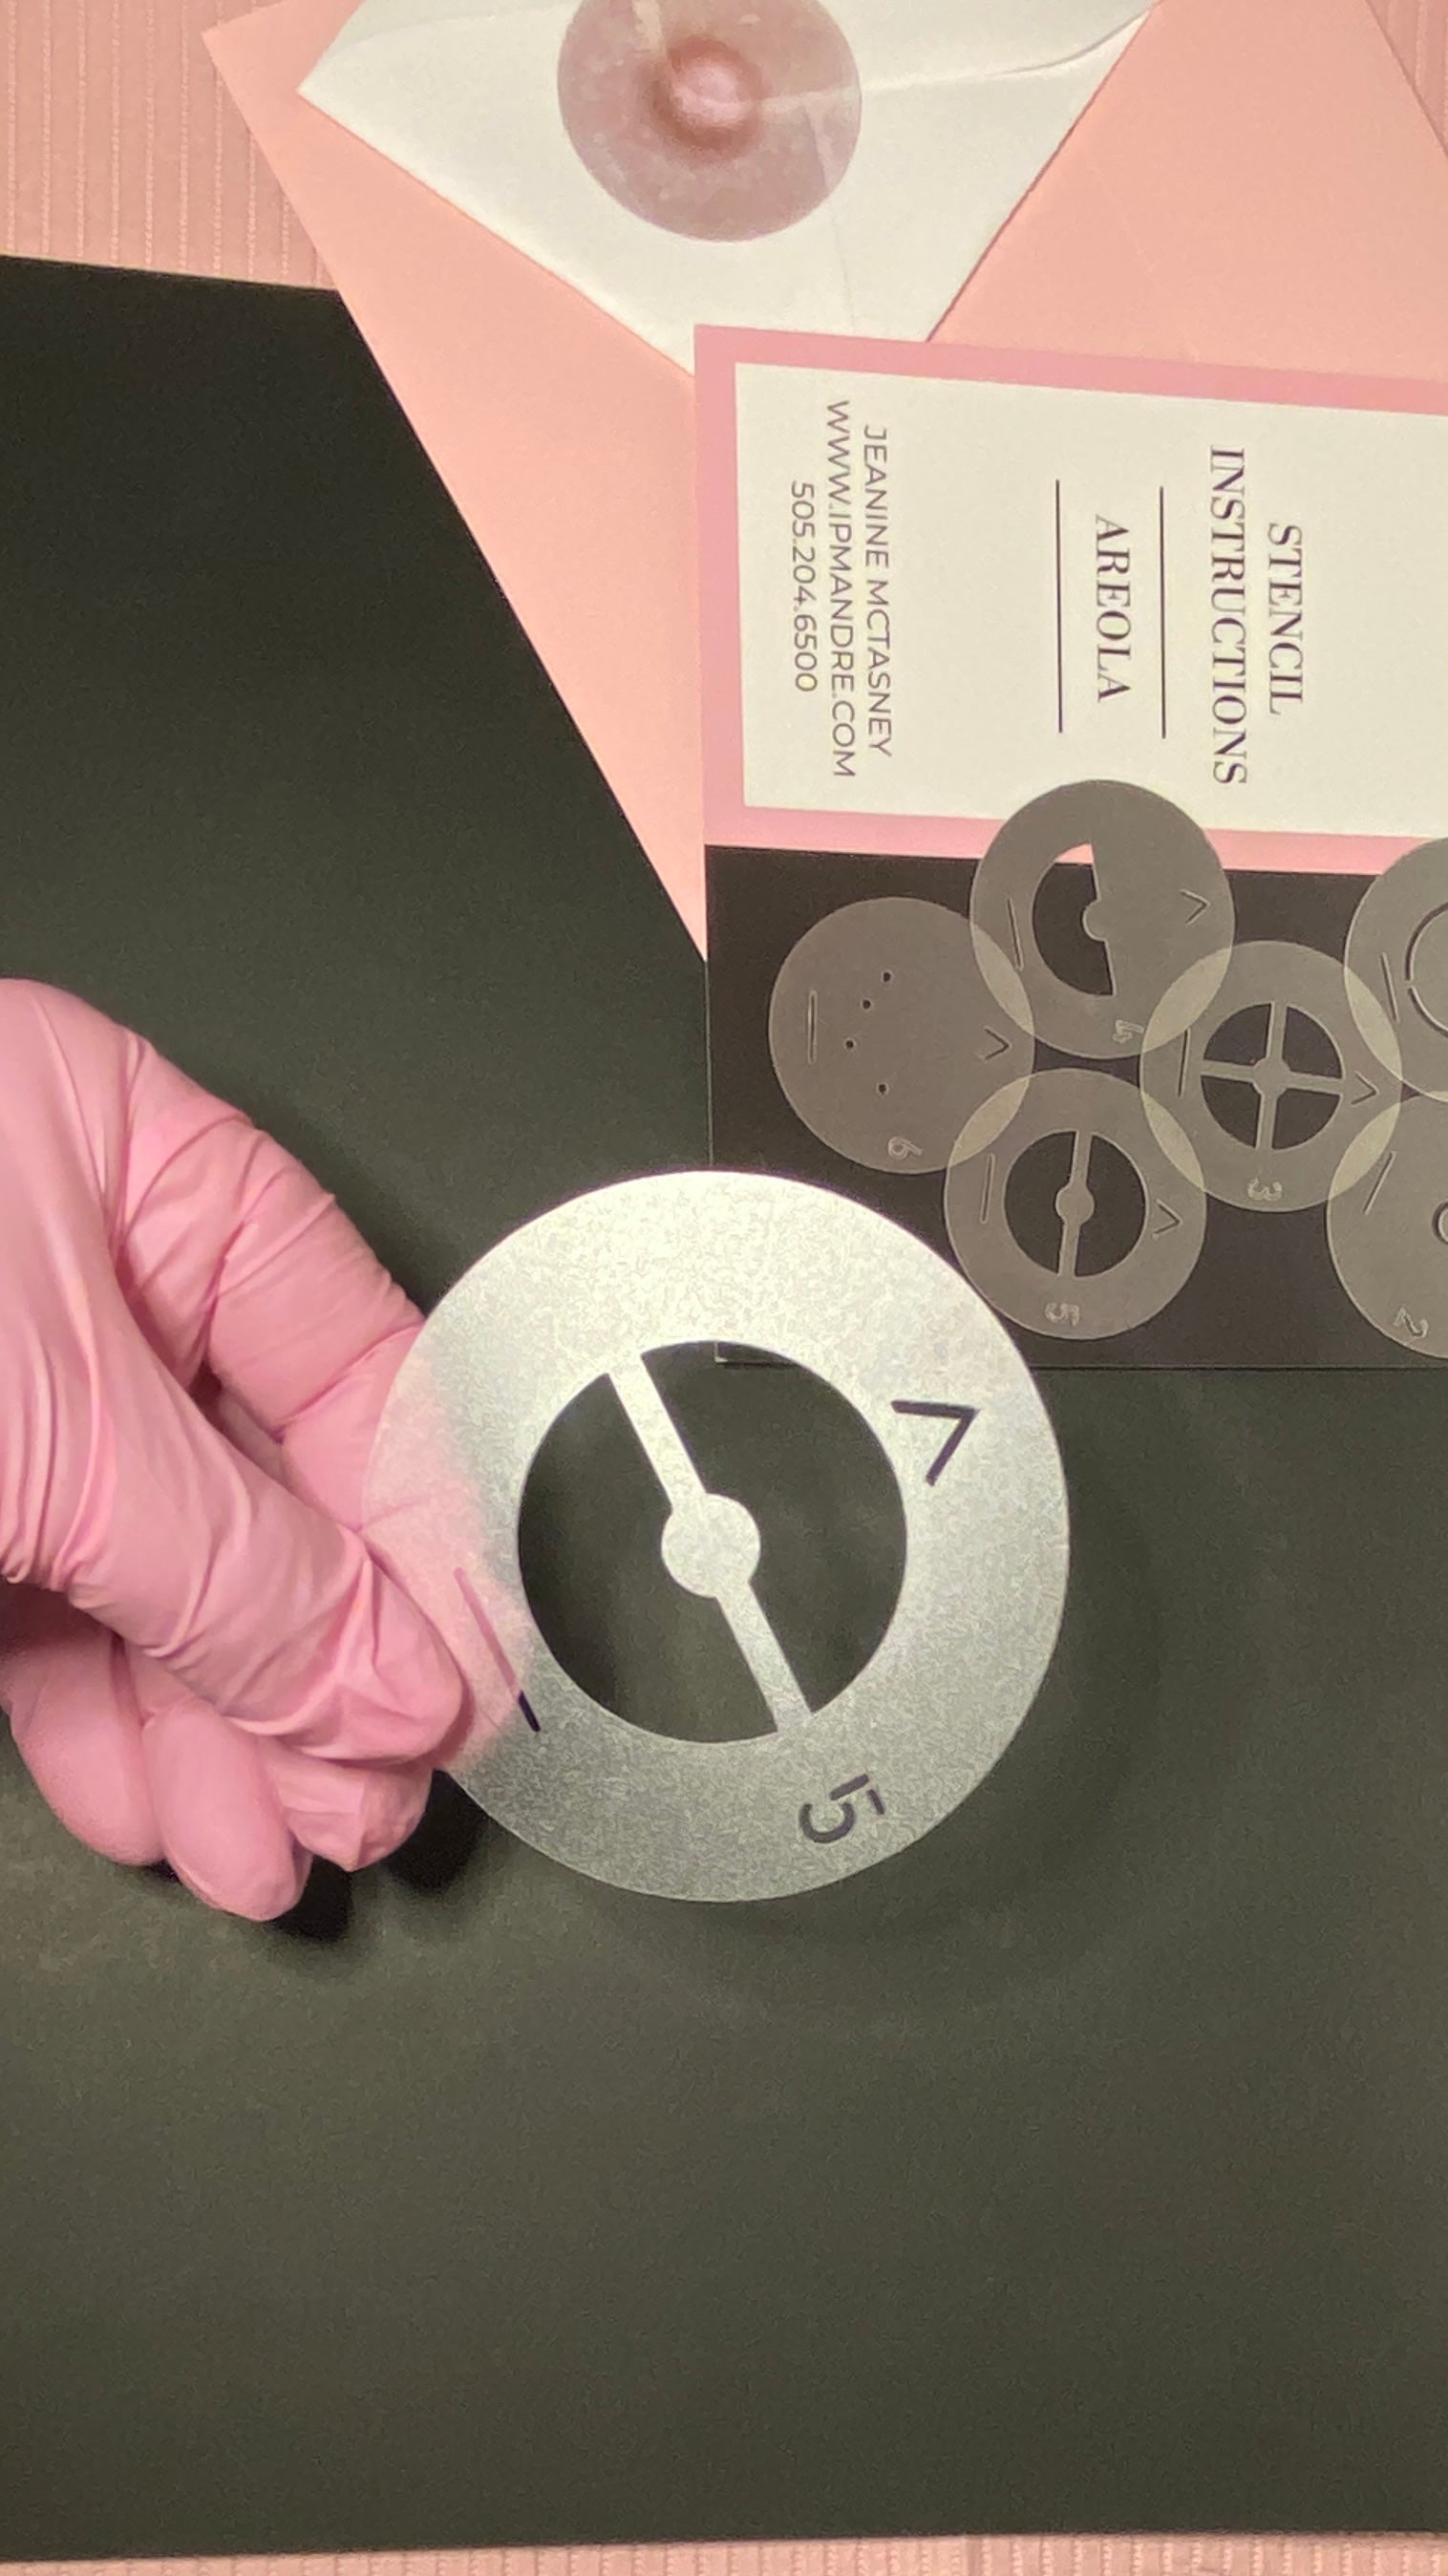

Creating a realistic, 3-D nipple/areola tattoo can be challenging — especially for new technicians learning the process. This 3-D Areola Tattoo Stencil Set is designed to simplify and guide you through each stage of areola restoration. With 6 professional-grade stencils and an 8-step workflow, you’ll have a clear visual roadmap while leaving space for your artistic interpretation and shading techniques to shine.

Made from 10mil polycarbonate film, these stencils are impact-resistant, clear, and durable — safe for practice pad work and even direct use during live procedures. They are steam autoclavable, alcohol-safe, and compatible with Sani-Cloth wipes, making them easy to clean and reuse safely. Ideal for PMU artists, medical tattooists, and professionals offering breast reconstruction finishing, scar camouflage, or restorative areola tattooing.